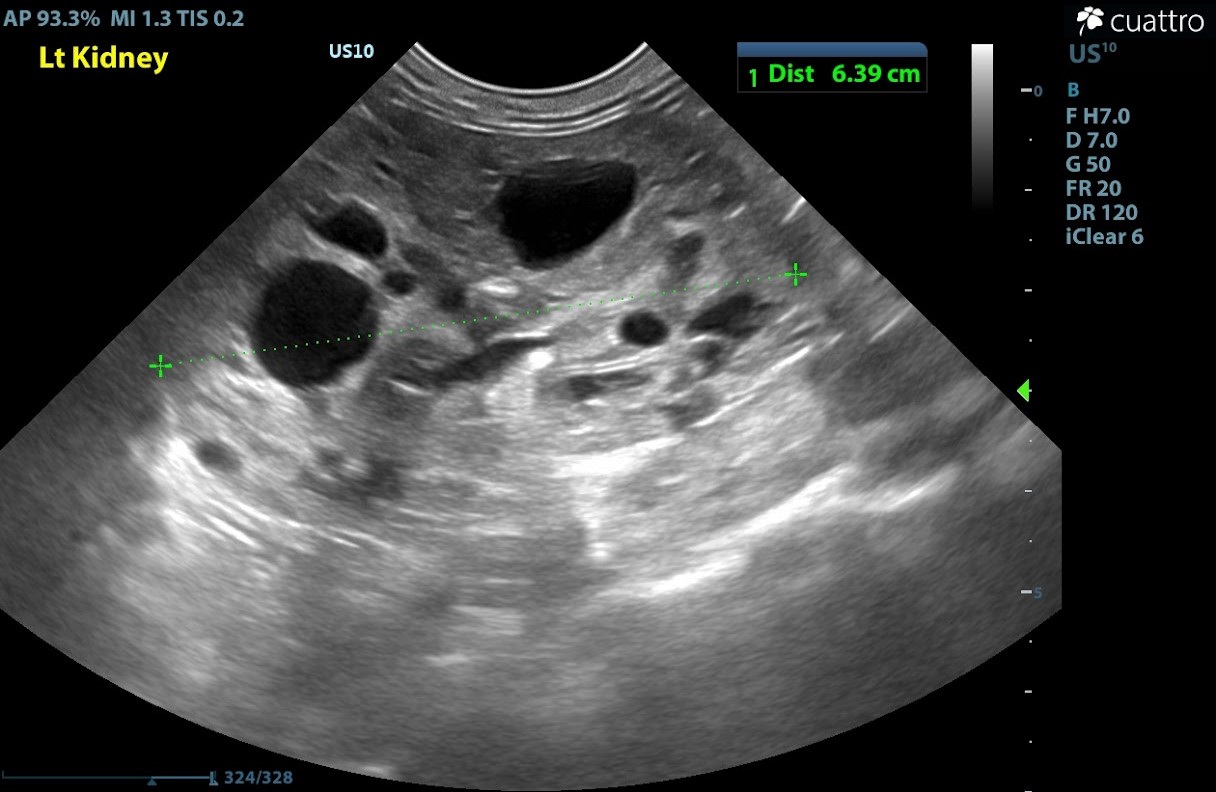

Sagittal view of the left kidney. Normal feline renal length is 3.2-4.2 cm. The left kidney appears to have enlarged size and overall normal shape, a significant number of anechoic cortical cystic lesions are present throughout the kidney.

Severely enlarged size (Lt/Rt = 6.9/6.0 cm) and normal overall shape with obliteration of normal renal architecture, there are TNTC variably sized anechoic cystic lesions throughout both kidneys. Adequate vasculature to the kidneys is appreciated. Bilateral pyelectasia visualized (Lt/Rt= 0.4/0.3 cm).